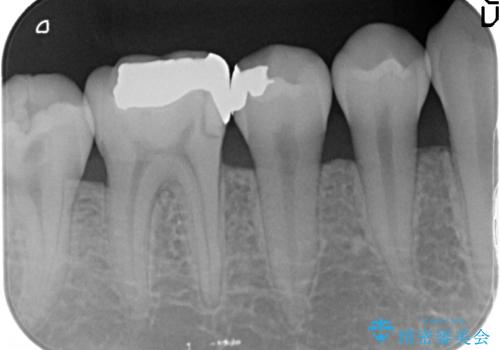

歯の神経を残す、丁寧な虫歯の除去

- 銀歯の劣化、歯のしみる症状の改善を求めて来院されました。

マイクロスコープ、拡大鏡を用いて治療を行うことで虫歯を取り切ることと必要以上に歯を削らず真剣を温存することのできる確率が高まります。

虫歯治療後の予後をより良くするために、虫歯を取り切ること精密な修復物の装着が必須となります。